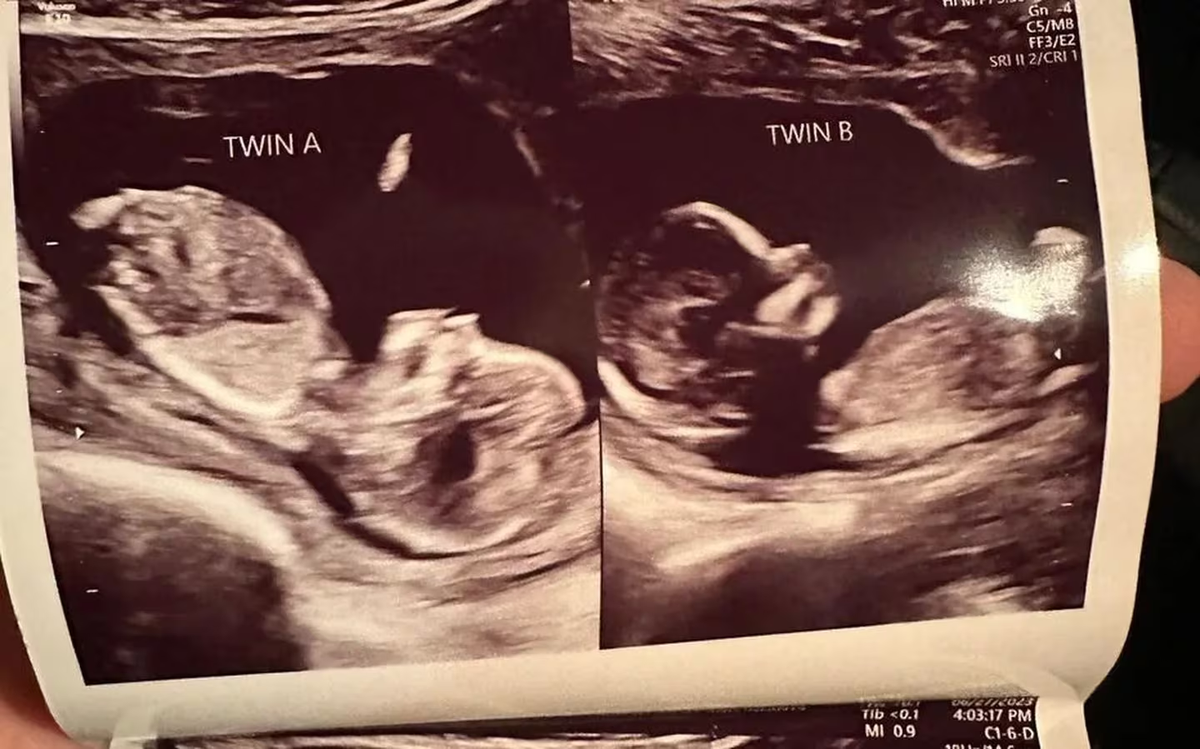

Fue durante una visita ecográfica de rutina de ocho semanas en mayo que la masajista y madre de tres hijos se enteró no solo de que esta vez iba a tener dos hijos, sino que había un feto presente en cada uno de sus úteros.

“¡Nos quedamos un poco impresionados! Durante esa primera ecografía, nos reímos mucho”, escribió en una publicación de Instagram.

Hatcher espera entrar en trabajo de parto y dar a luz natural con medicamentos tanto a la beba A como a la beba B, o “las niñas”, como ella las llama cariñosamente, con una fecha de parto para Navidad. Se dice que ambos embriones están “prosperando”.